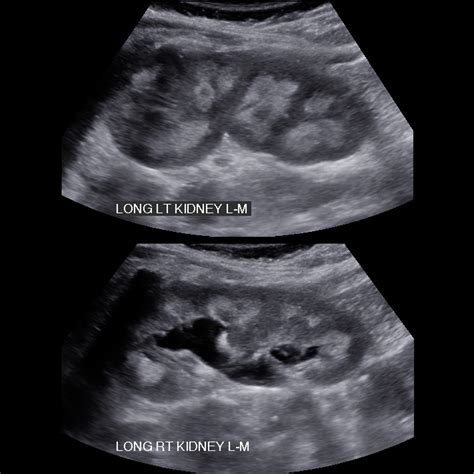

Interpreting the results of a Medullary Sponge Kidney USG requires expertise in radiology. The key findings that indicate Medullary Sponge Kidney include:

• Cystic dilatation of the collecting ducts in the renal medulla.

• Enlarged kidneys with a spongy appearance.

• Presence of kidney stones or calcifications.

• Thickening of the renal parenchyma.

These findings help in confirming the diagnosis of Medullary Sponge Kidney and guiding further management strategies.

Case Study 1: A 35-year-old patient presented with recurrent urinary tract infections and flank pain. An initial USG revealed cystic dilatation of the collecting ducts, confirming the diagnosis of Medullary Sponge Kidney. The patient was started on antibiotics and hydration therapy, which significantly reduced the frequency of infections and improved symptoms.

• medullary sponge kidney ultrasound images

• medullary sponge kidney ultrasound appearance

• sponge kidney ultrasound images